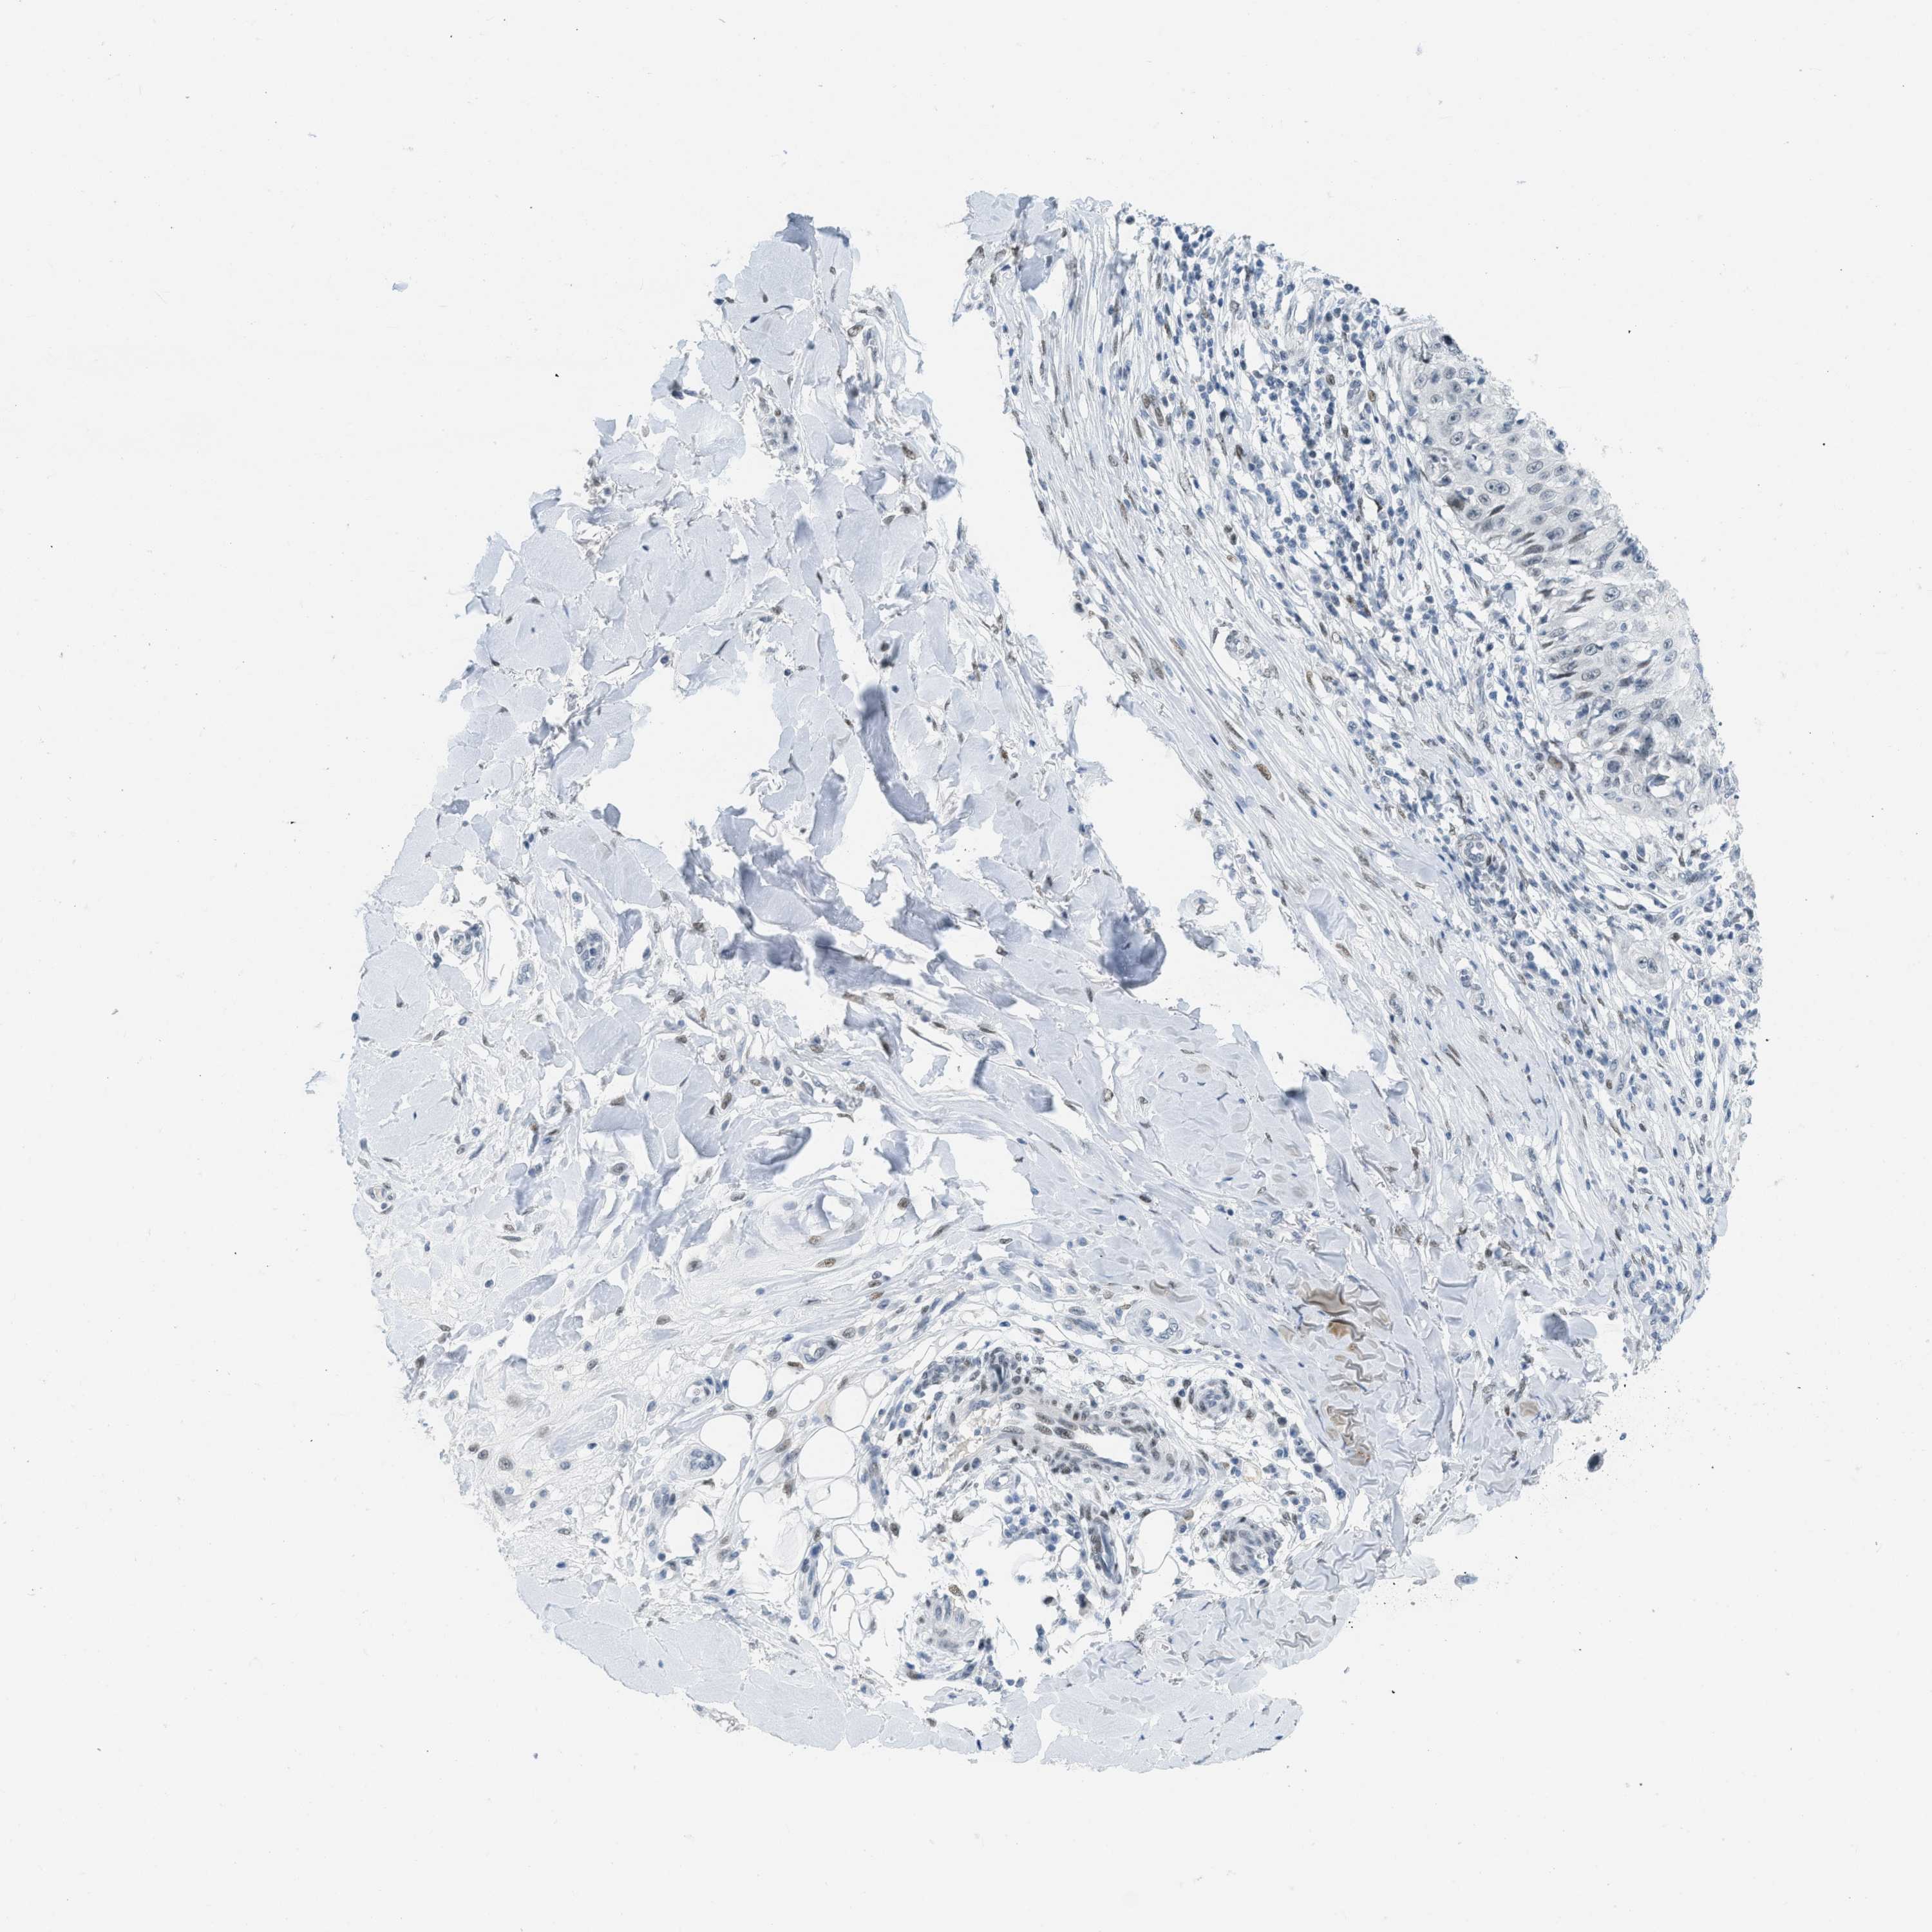

SKIN CANCER - Protein expressioni

A mouse-over function shows sample information and annotation data. Click on an image to view it in a full screen mode. Samples can be filtered based on level of antibody staining by selecting one or several of the following categories: high, medium, low and not detected. The assay and annotation is described here.

Each image is clickable and will lead to virtual microscopy that enables deeper exploration of all samples and also displays staining intensity scores, fraction scores and subcellular localization as well as patient and tissue information for each sample.

Antibody HPA003505

Squamous cell carcinoma, NOS

Basal cell carcinoma

Squamous cell carcinoma in situ, NOS

Squamous cell carcinoma, metastatic, NOS